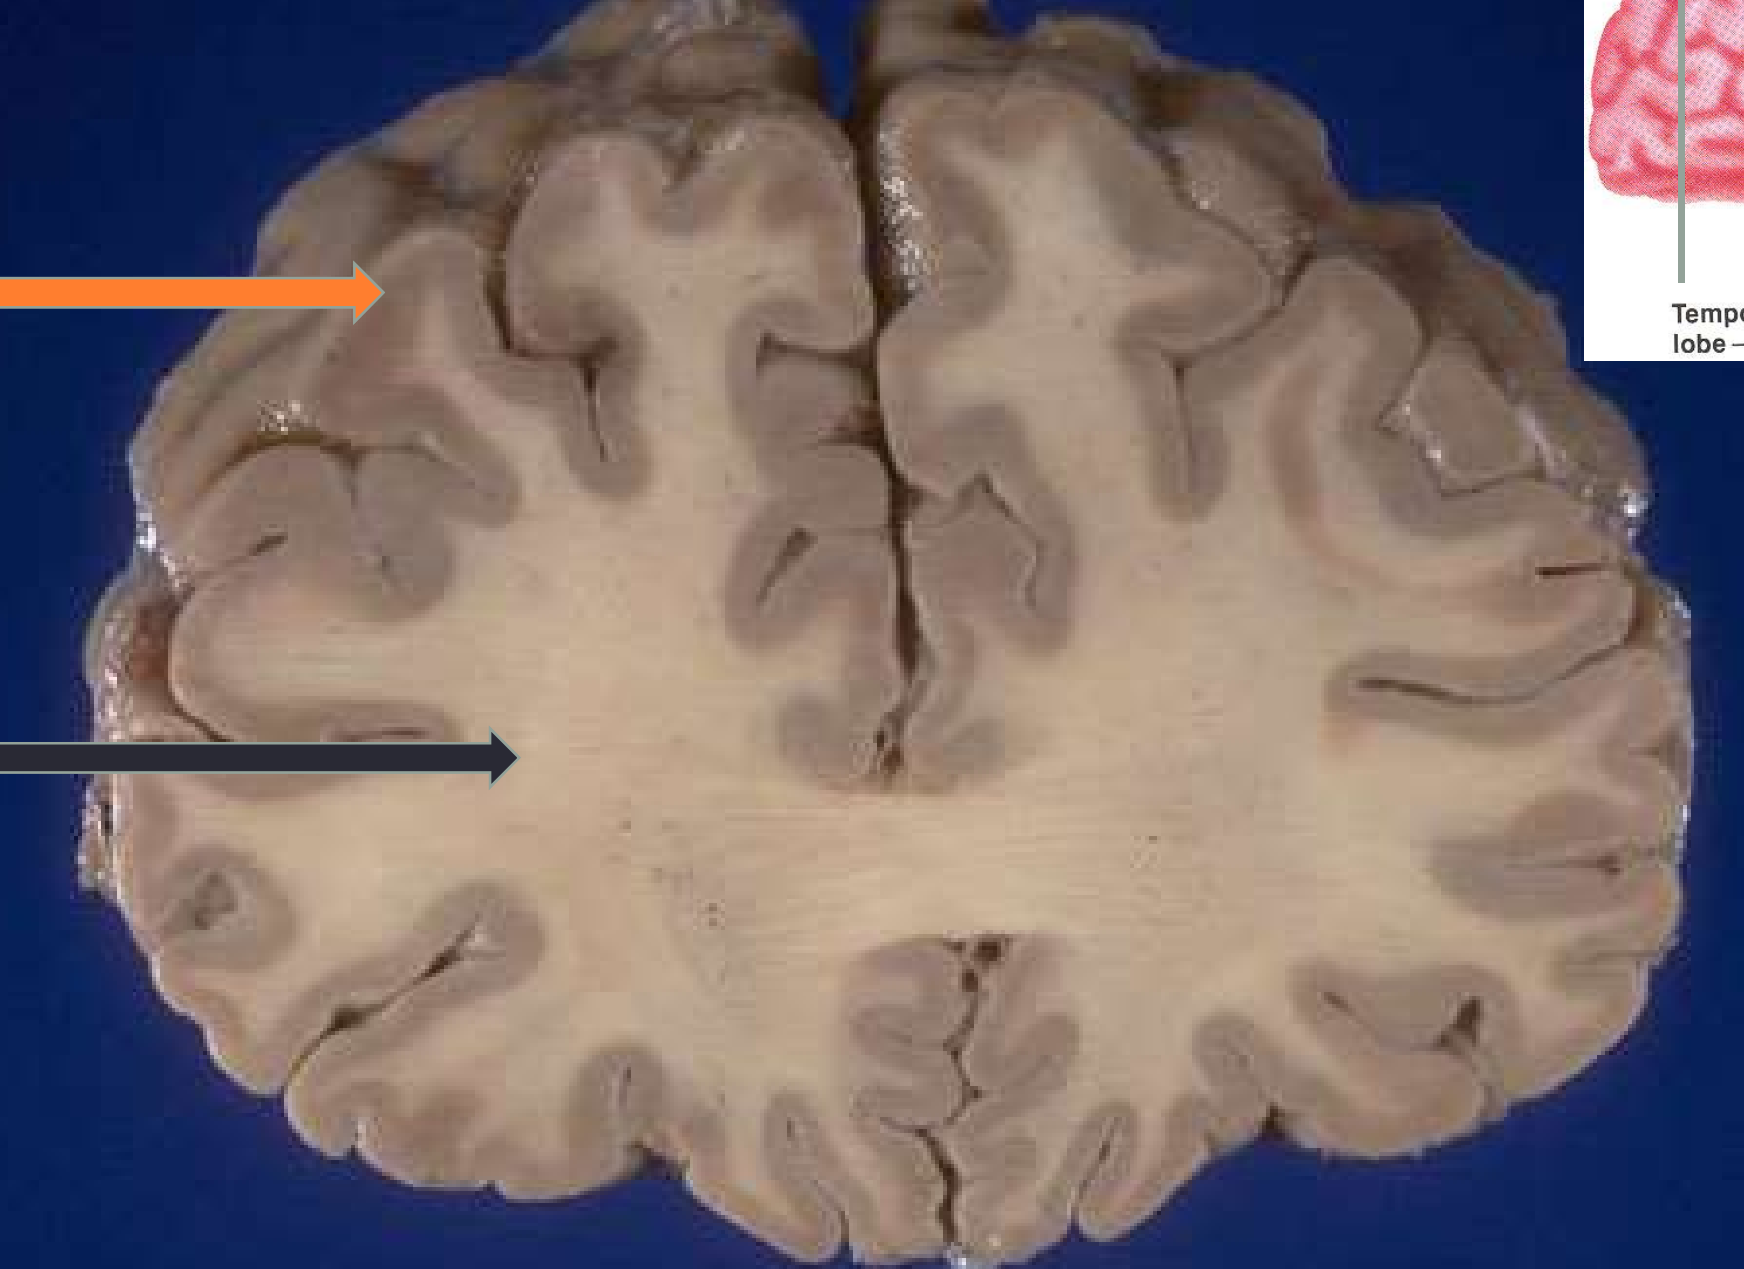

Identifiez la matière grise et la matière blanche

Orange = matière grise

Noir = matière blanche